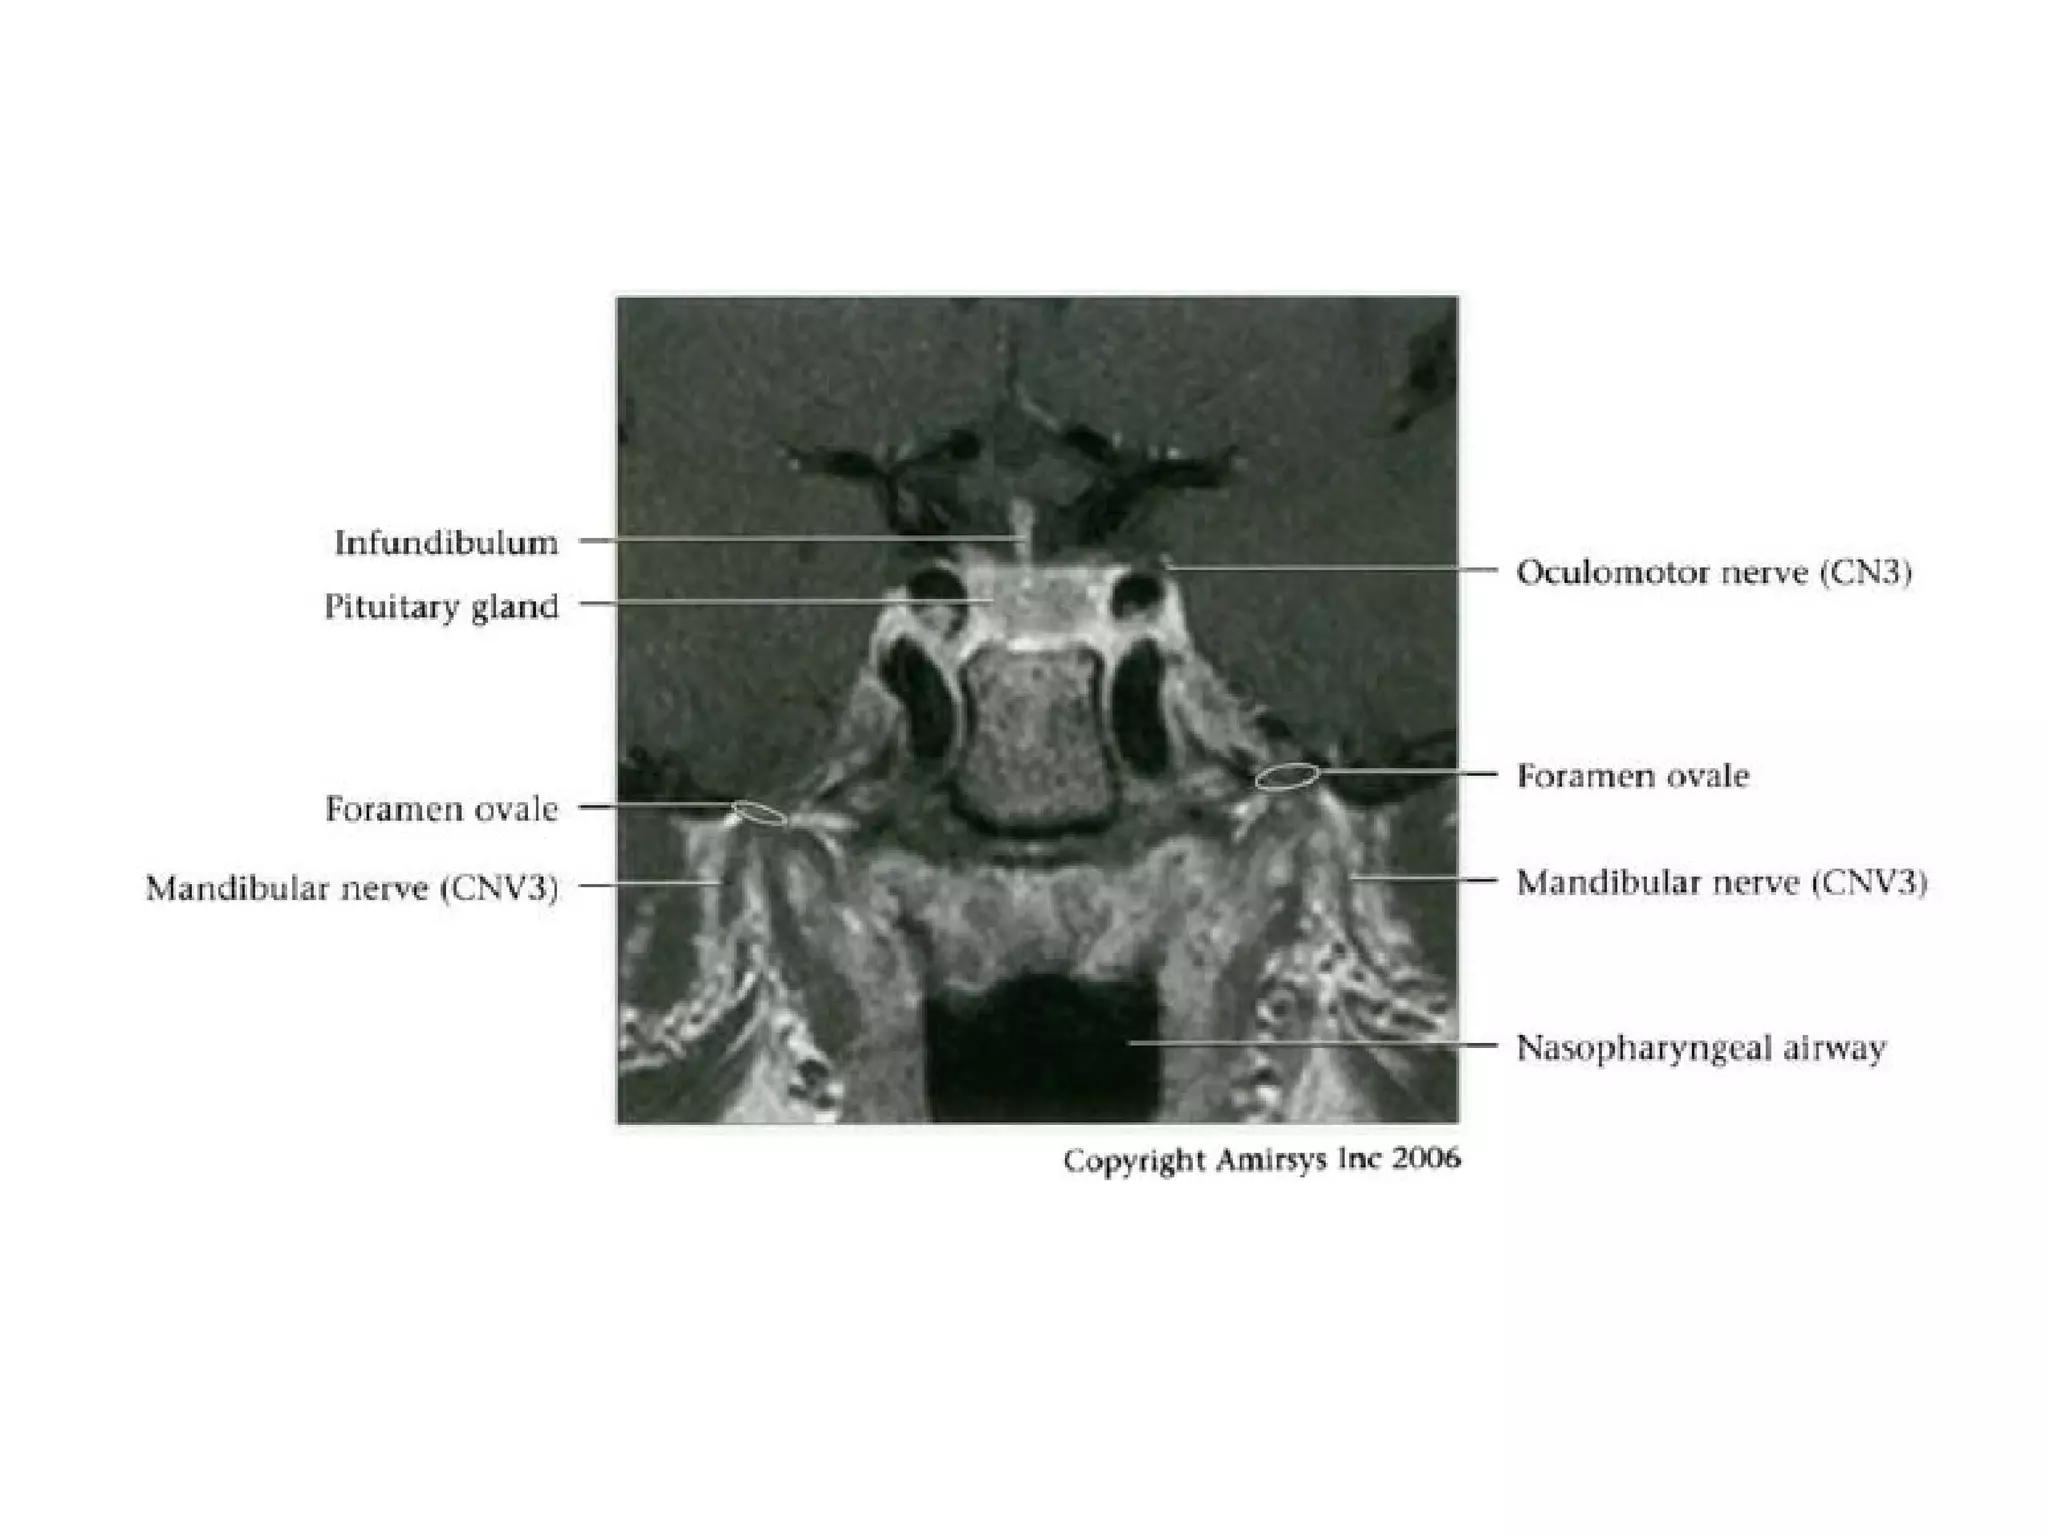

Cranial Nerve V:

The Trigeminal Nerve

• The trigeminal nerve is the largest cranial nerve.

• It is composed of a large sensory root that

runs medial to a smaller motor root.

• The roots emerge from the lateral midpons and

travel anteriorly through the prepontine cistern

and the porus trigeminus to the Meckel

(trigeminal) cave, a CSF-containing pouch in the

middle cranial fossa.

• Because the trigeminal nerve is large and its

course proceeds straight forward from the lateral

pons, it is easy to recognize on most MR

images.

• In the Meckel cave, the nerve forms a meshlike web that

can be visualized only with high-resolution imaging.

• Along the anterior aspect of the cavity, the trigeminal

nerve forms the trigeminal (gasserian) ganglion before

splitting into three subdivisions.

• The ophthalmic (V1) and maxillary (V2) divisions of the

nerve move medially into the cavernous sinus and exit

the skull through the superior orbital fissure and foramen

rotundum, respectively.

• The mandibular division (V3), which includes the motor

branches, exits the skull inferiorly through the foramen

ovale.

Trigeminal nerve.

Axial 0.8-mm-thick SSFP MR image shows the sensory

(arrowhead) and motor (large arrow) roots of the trigeminal

nerve

where they cross the prepontine cistern and enter the Meckel

cave (small arrows).

Coronal 0.8-mm-thick SSFP MR image at the level of the Meckel

cave shows the complex web of trigeminal nerve branches

(arrows), which coalesce anteriorly to form the gasserian

ganglion. The temporal horn of the lateral ventricle (arrowhead)

is also shown.